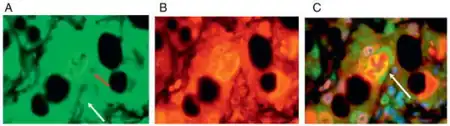

Some signs and pathological changes in liver histology include:

- Mallory's hyaline body – a condition where pre-keratin filaments accumulate in hepatocytes. This sign is not limited to alcoholic liver disease, but is often characteristic.[6]

- Ballooning degeneration – hepatocytes in the setting of alcoholic change often swell up with excess fat, water and protein; normally these proteins are exported into the bloodstream. Accompanied with ballooning, there is necrotic damage. The swelling is capable of blocking nearby biliary ducts, leading to diffuse cholestasis.[6]

- Inflammation – neutrophilic invasion is triggered by the necrotic changes and presence of cellular debris within the lobules. Ordinarily the amount of debris is removed by Kupffer cells, although in the setting of inflammation they become overloaded, allowing other white cells to spill into the parenchyma. These cells are particularly attracted to hepatocytes with Mallory bodies.[6]